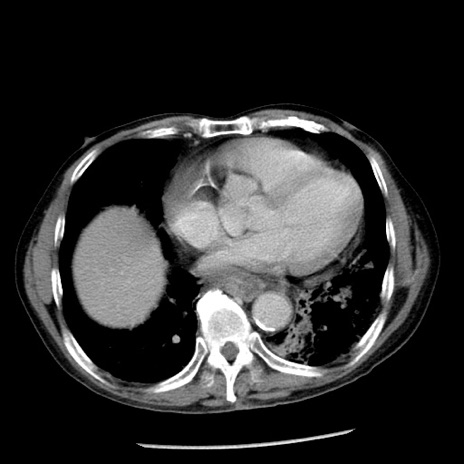

症例26(横断像)

【症例】80歳代男性

【主訴】嘔吐

【現病歴】昨晩2回嘔吐あり、今朝になっても嘔吐あり。来院。

【既往歴】胃潰瘍

【身体所見】意識清明、BT 37.6℃、BP 166/95mmHg、HR 100bpm、SpO2 97%、腹部:平坦・軟、腸蠕動音聴取良好、圧痛なし。

【データ】WBC 21900、CRP 1.46